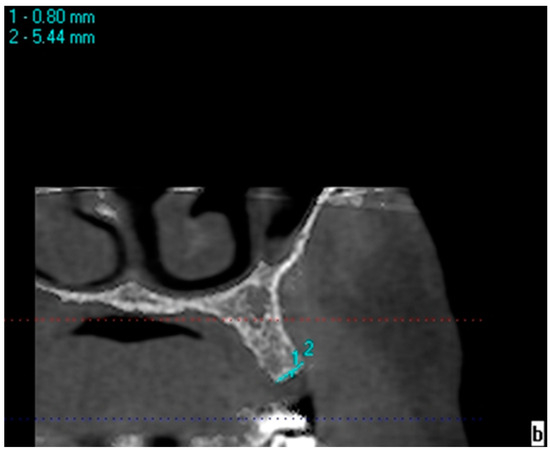

Bone measurements in areas with one missing tooth were made on 1.2 mm thick cross-sectional CBCT images obtained using the KaVo eXamVision (KaVo Dental GmbH, Biberach, Germany) program. Bone width was measured at the midpoint of the mesiodistal width of the edentulous region, 0.8 mm below the ridge crest, on the line connecting the vestibule/palatal and buccal/lingual walls (Figure 1). Bone width measurements at 2.8, 4.8, and 6.8 mm depths were performed following the same protocol as the bone width measurements performed at a 0.8 mm depth. The horizontal and vertical lines at 0.8 mm were used as the reference for the calculation of the depths. The protocol for edentulous crest measurements was applied in the same way for symmetrical toothed side measurements. Bone width measurements of symmetrical teeth were made with reference to the line that passes 0.8 mm below the lower crest of one of the buccal/vestibule and lingual/palatal bone walls (Figure 2). Bone heights were obtained through linear measurement of the distance between the reference point at the crest (the midpoint of the line at which bone width measurements were made) and the mandibular canal, maxillary sinus, mental foramen, and nasal floor. Intra-examiner reliability was calculated to assess the reliability of the measurements. The measurements in this study were performed by a single investigator specializing in oral and maxillofacial radiology. The second measurements were performed 4 weeks after the first measurement.

Figure 2. Measurement of bone width in the right second premolar area.